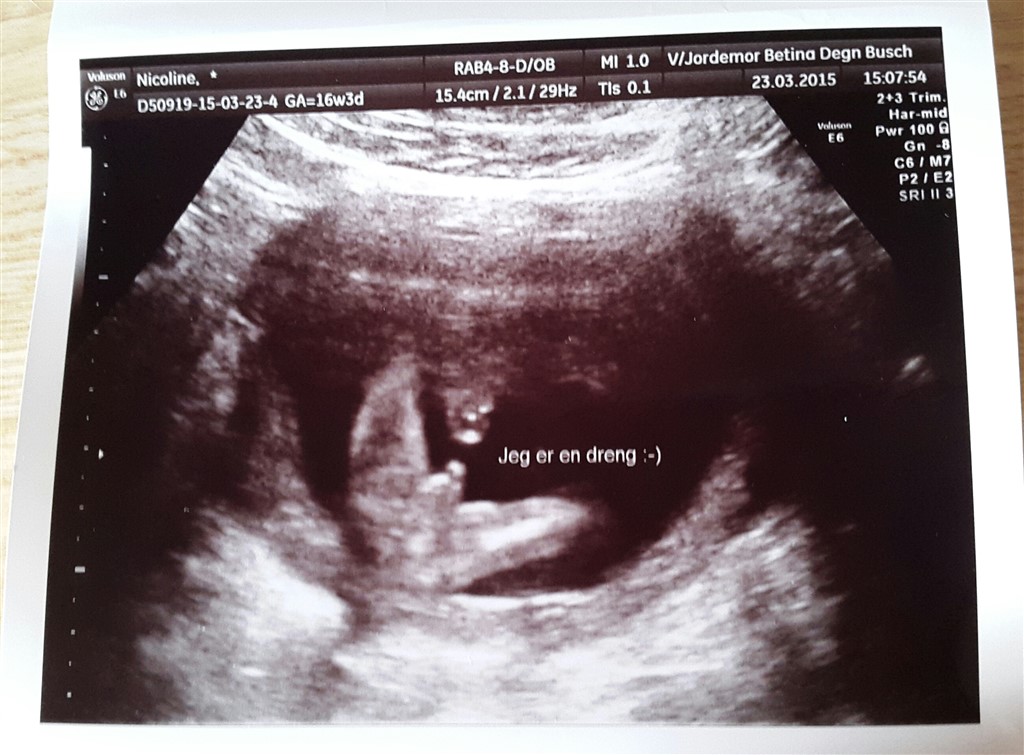

Vi fik hos Barn i vente i Slagelse, hun er virkelig sød og super dygtig . . Jeg var til kønscanning da jeg var 16+3 og der var og er ingen tvivl på det perfekte billede hun fik frem, at vi venter os en lille dreng . . Hun har arbejdet som jordemoder i omkring 10 år og hun har aldrig taget fejl på en kønscanning, der er ihvertfald aldrig nogen der har klaget tilbage

. . Hvis kønnet ikke er muligt at se på dagen man er der, så tilbyder hun en ny gratis scanning . .

Jeg er i dag 24+3